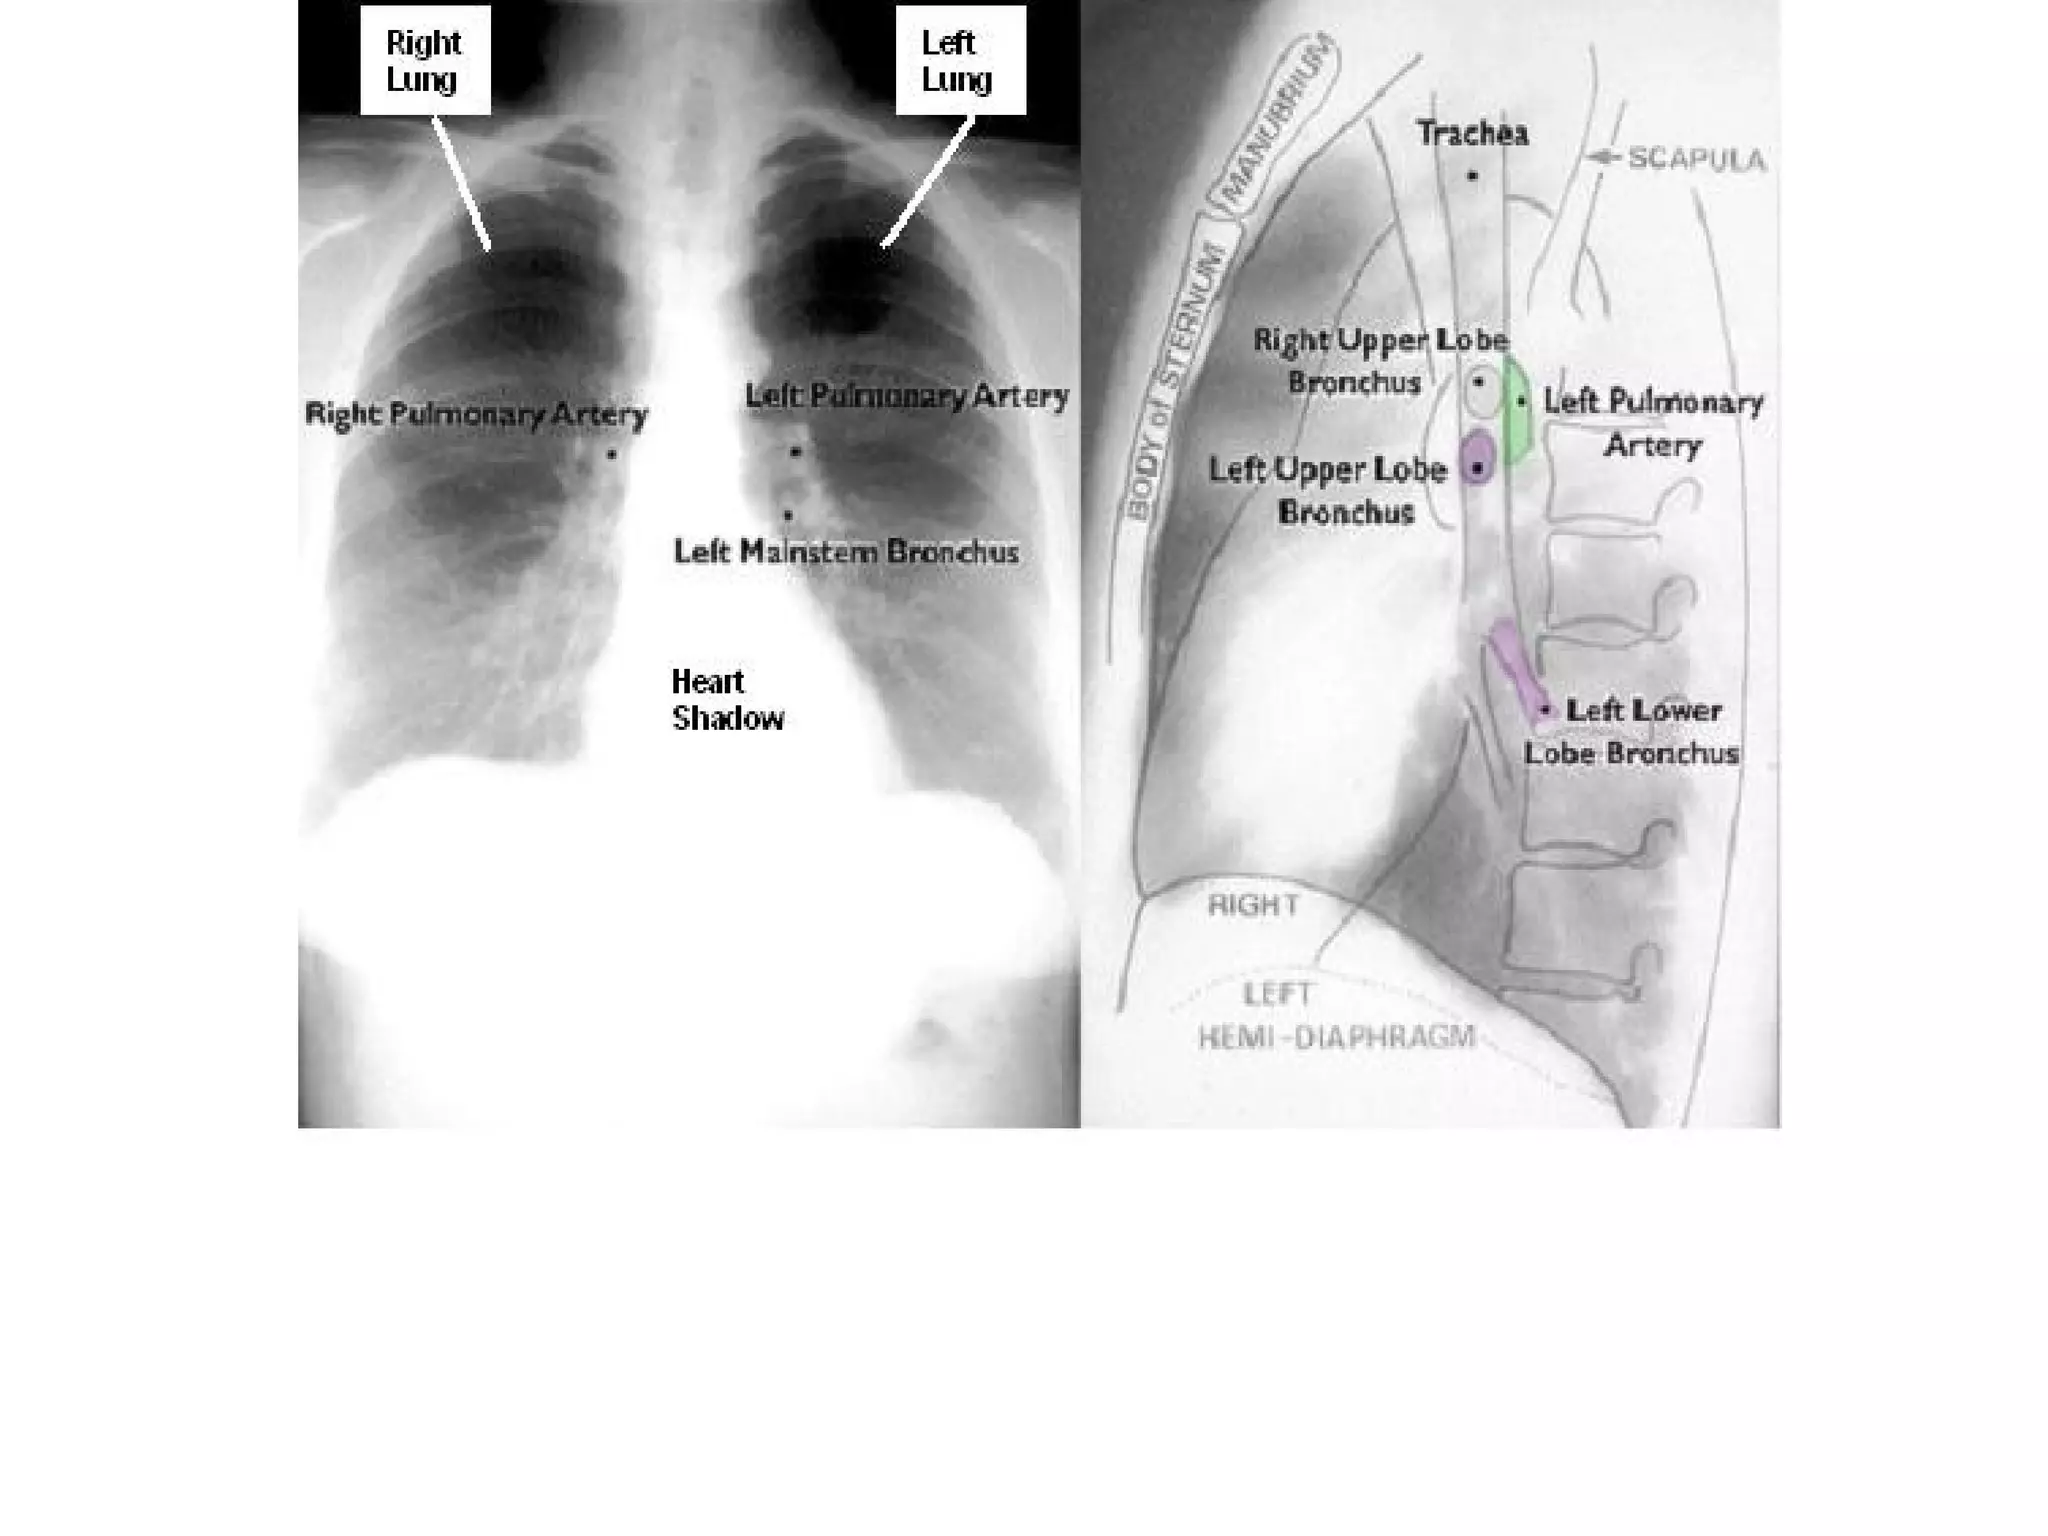

• The PA view

PA view                   AP view

The hila

In 97% of subjects the left hilum is higher

than the right. The hila should be of equal

density and similar size with clearly

defined concave lateral borders.

The lower lobe vessels are larger than those

of the upper lobes in erect position.

The right main bronchus is shorter, steeper

and wider than the left.

The hila In 97%of subjects the left hilum is higher than the right. The hila should be of equal density and similar size with clearly defined concave lateral borders. The lower lobe vessels are larger than those of the upper lobes in erect position. The right main bronchus is shorter, steeper and wider than the left.